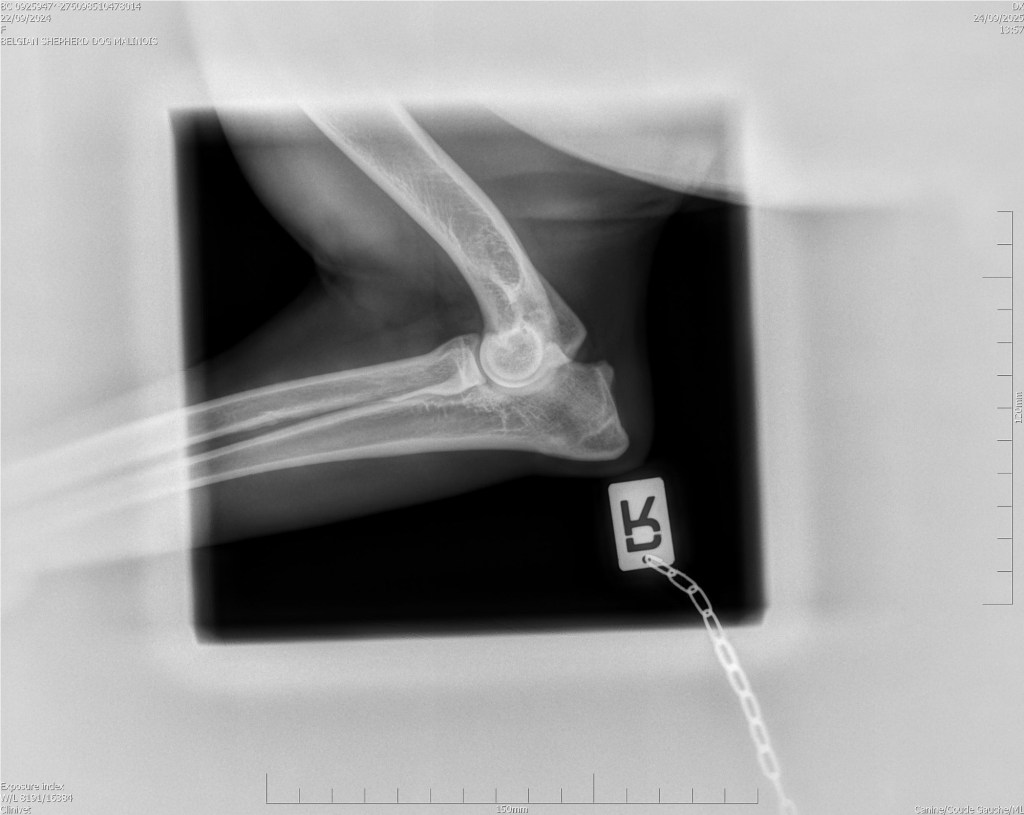

Hips 2/3

Elbows 0/0